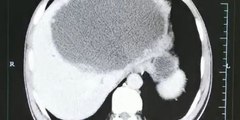

Après avoir mangé du poisson cru, il a eu le foie infesté de vers